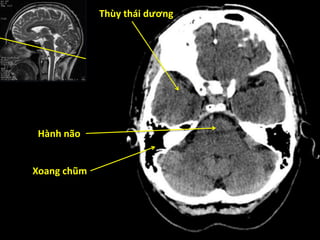

Thùy thái dương

Tiểu não

Cầu não

Não thất tư

Bể trên yên

Khe Sylvius

Hành não

Xoang chũm

Thùy trán Thùy tháidương Tiểu não Cầu não Não thất tư Bể trên yên Khe Sylvius

Thùy thái dương Hànhnão Xoang chũm